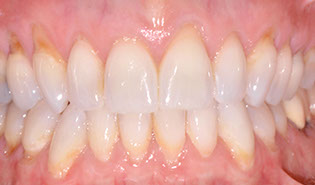

3.2 Immediate Load Prosthetics (All-on-4)

This part of the course covers the methods of diagnosis, practical treatment planning, pre-surgical prosthodontics, imaging, armamentarium, and clinical techniques needed for this exciting treatment modality. Crucial to this treatment modality is the understanding of the biomechanical aspects and functional loading of the immediate full arch prostheses. The aesthetic and phonetic requirements, space requirements, laboratory communication, insertion techniques post-operative follow-up and hygiene requirements are key to this treatment.

Aesthetic and phonetic requirements

Establish a systematic and organised approach to the prosthetic techniques for this modality of treatment

Complete sequential treatment planning from patient examination to post insertion follow up and protocols